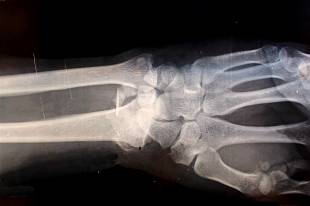

골량 감소와 함께 미세 구조가 동시에 손상되는 전신성 골격 질환으로 분류됩니다. 이 주제를 이해하기 위해서는 질환의 성격을 정확히 파악해야 합니다. 뼈 속의 해면골이 치밀한 격자 형태를 잃고 느슨해지면서 압력 분산 능력이 떨어집니다. 이는 단단한 콘크리트 내부에 균열이 퍼지는 과정과 유사합니다.